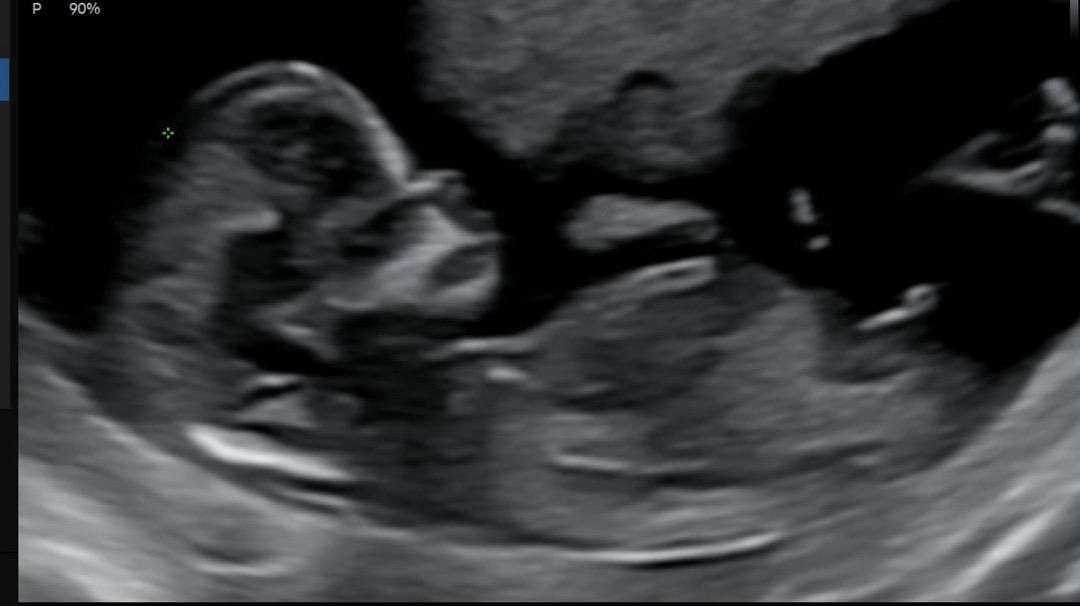

12주4일입니다. 건강만 하면 좋겠다 생각했는데, 그래도 궁금하긴하네요ㅠㅋㅋ 각도법 도와주시겠어요?? 여아일까요 남아일까요??